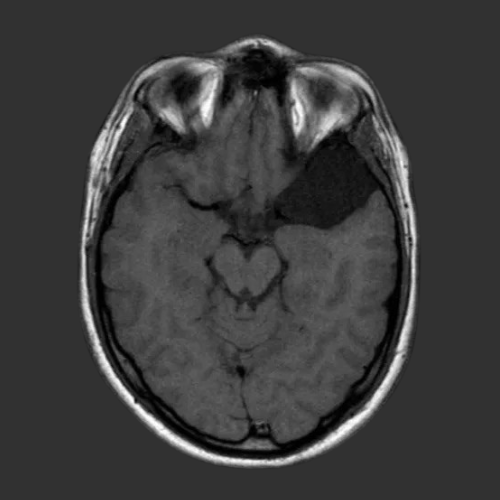

Tumor cerebral

Un tumor cerebral es una masa formada por el crecimiento de células anormales o proliferación incontrolada de células en el cerebro.

Quistes aracnoideos intracraneales

Los quistes aracnoideos (QA) son colecciones extra cerebrales de carácter benigno formadas por líquido cefalorraquídeo (LCR)